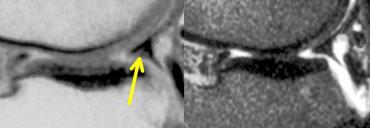

TRÁI: Dấu hiệu sụn chêm vắng mặt hoặc rỗng trên ảnh đứng dọc. PHẢI: Ảnh axial cho thấy rách xuyên tâm hoàn toàn tạo ra khuyết hổng trong sụn chêm.

Nếu chụp ảnh rách xuyên tâm hoàn toàn dọc theo chiều dài đường rách, bạn sẽ thấy hình ảnh sụn chêm vắng mặt hoặc rỗng.

Các rách xuyên tâm hoàn toàn này mở ra và tạo ấn tượng như có một phần sụn chêm bị mất.

Tuy nhiên, bạn sẽ không tìm thấy mảnh sụn chêm di lệch. Đây đơn giản là sự tách rời của các phần sụn chêm.

Rách chân bám sụn chêm: trên ảnh đứng dọc có dấu hiệu sụn chêm vắng mặt hoặc rỗng kề cạnh dây chằng chéo sau tại vị trí lẽ ra phải thấy chân bám sụn chêm. Trên ảnh coronal, rách chân bám sụn chêm được xác nhận.

Rách chân bám sụn chêm

Rách chân bám sụn chêm là rách xuyên tâm xảy ra tại vị trí chân bám của sụn chêm.

Bình thường, khi quan sát dây chằng chéo sau trên ảnh đứng dọc, bạn phải thấy một phần đáng kể của sừng sau sụn chêm trên lát cắt đó hoặc lát cắt kề cạnh.

Nếu không thấy, đó là dấu hiệu sụn chêm vắng mặt hoặc rỗng, gợi ý rách xuyên tâm.